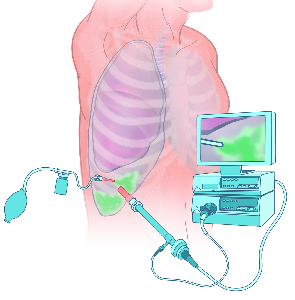

Detailreiche Fotografien aus der medizinischen Praxis ergänzen die Texte; moderne, genaue,

wissenschaftliche Zeichnungen geben Einblick in die Anatomie und die Funktion der Lunge und

anderer Organe.